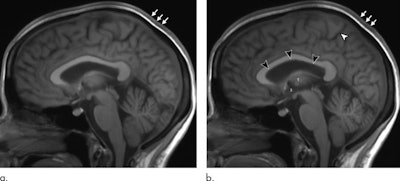

MRI scans of 11 astronauts performed the day after their return from extended time in space have revealed significant changes in brain volume and cerebrospinal fluid (CSF) flow. The astronauts also saw their pituitary glands shrink, according to a study published April 14 in Radiology.

When the researchers compared MR images before time in space and one day after the astronauts' return, they discovered a number of statistically significant changes, including the following:

- Increased mean total volume in the brain of 28 mL (p < 0. 001), most of which was due to white matter of 26 mL (p < 0.001)

- Increased mean enlargement of lateral ventricles of 2.2 mL (p < 0001)

When brain volume and CSF were combined, the statistically significant increases held steady for one year. In addition, six astronauts (55%) showed a significant decrease in the mean pituitary gland of 5.3 mm, compared with 5.9 mm in the preflight MRI (p < 0.01).